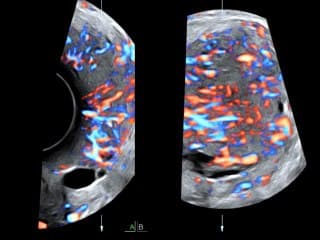

La médiathèque du Collège Français d'Échographie Fœtale (CFEF) constitue l'une des plus importantes collections de ressources vidéo dédiées à l'échographie fœtale en France. Avec plus de 3 261 vidéos, elle couvre l'ensemble des thématiques liées à la pratique échographique prénatale.

Vous y trouverez des conférences présentées lors des congrès nationaux et internationaux, des cours magistraux dispensés par des experts reconnus, des démonstrations pratiques sur des cas cliniques réels, ainsi que des podcasts et tables rondes sur les dernières avancées de la spécialité.